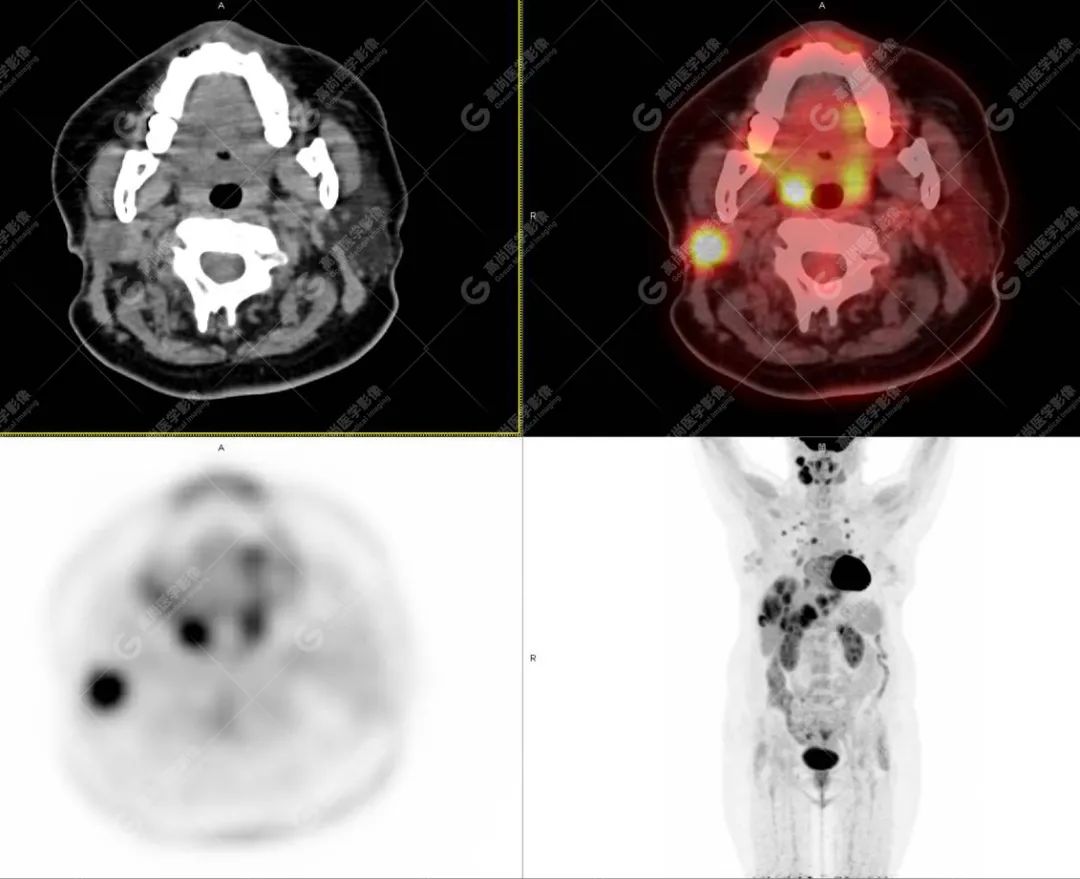

影像诊断:1. 结合病史,右颈部神经鞘瘤(低度恶性)术后改变,右侧颈部稍低密度及等密度结节,代谢异常增高,考虑为肿瘤复发并右颈部淋巴结转移,建议活检。 2. 双侧肺门及纵隔(4R 区)多发肿大淋巴结,代谢异常增高,考虑为转移。 3. 双肺多发大小不等实性结节,部分代谢增高,考虑为转移。 4. 肝脏多发低密度结节及肿块,代谢异常增高,考虑为转移。 5. 右侧第 8 前肋骨骨质破坏,代谢异常增高,考虑为转移。

随访病理(右侧颈部结节):血管肉瘤